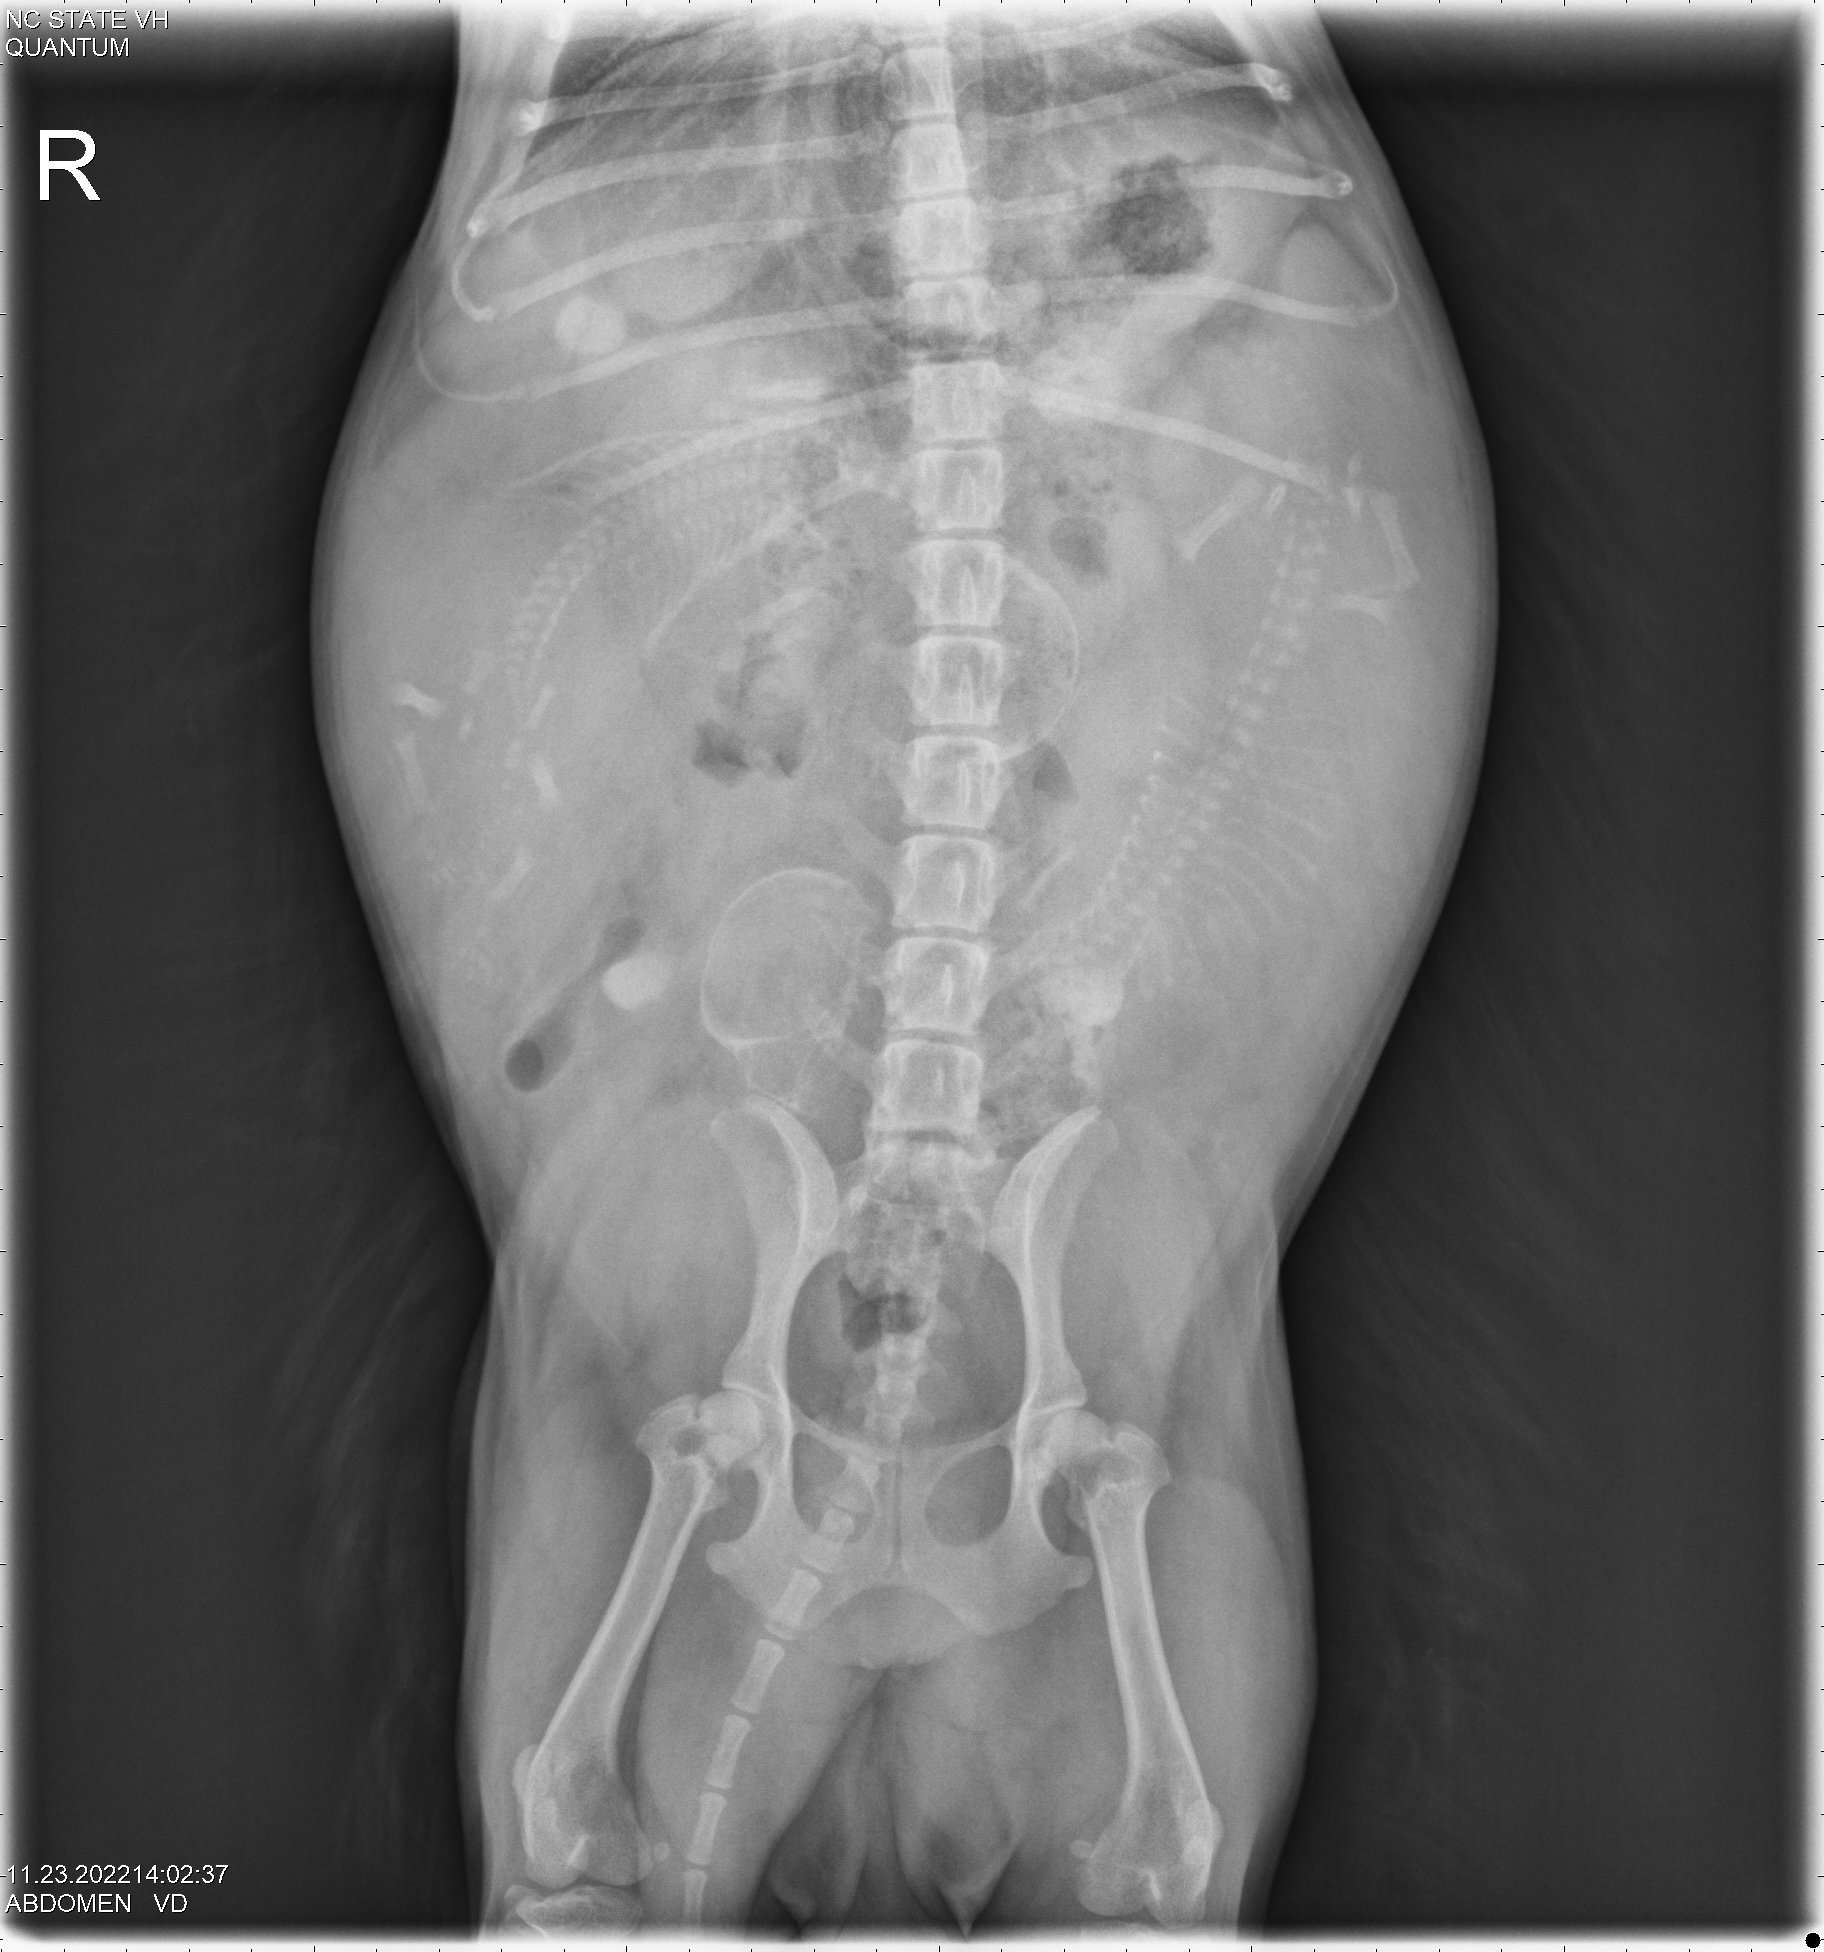

23 Nov

Since I was travelling, my petsitter was kind enough to take Siri to NC State for x-rays to count the number of puppies. The x-rays showed two puppies.

By measuring the size of the puppies' skulls and the width of Siri's pelvic opening, it was determined that the puppies should be able to fit through Siri's pelvis. Thus Siri might be able to have the puppies naturally (free-whelp), rather than needing a cesarean section (c-section). The rule of thumb is that if there is only one puppy, a c-section is almost always necessary; whereas if there are three or more puppies, one should try to free-whelp. If there are only two puppies, it is not clear what to do.